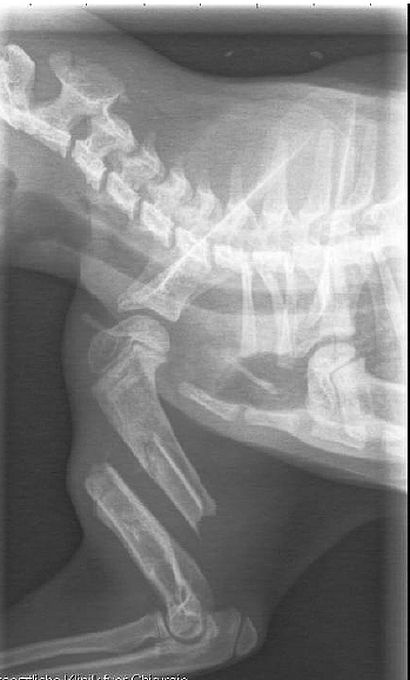

Das Beinchen sah nicht gut aus, daher wurde sie gleich in die Tierklinik gebracht. Dort stellte sich heraus, dass sie sich den Oberarm

gebrochen und sich dann auch noch der Nerv auf den Knochen aufgespießt hatte. Da der Bruch schon 8-10 Tage alt war, war dieser Nerv auch schon mit dem Knochen verwachsen.